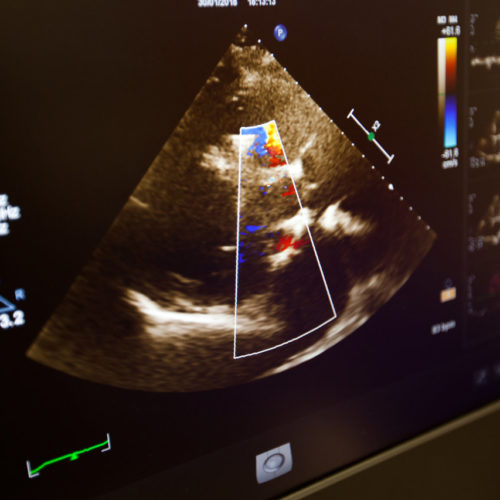

Transthoracic and transoesophageal echocardiogram

An echocardiogram test is an ultrasound scan of the heart, which provides accurate pictures of the heart muscle, the heart chambers and structures within the heart such as the valves.